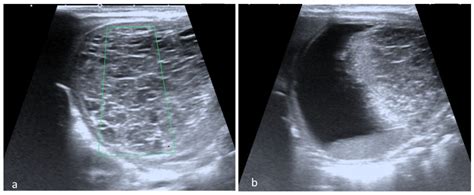

When a physician suspects a dermoid cyst ovary, they will utilize specific diagnostic tools to confirm the presence, size, and location of the mass. Imaging is the gold standard for diagnosis because the specific contents of these cysts—such as fat, calcium (teeth/bone), and fluid—have distinct appearances on scans.

CT Scan Provides detailed images to assess the composition of the cyst and identify calcifications.